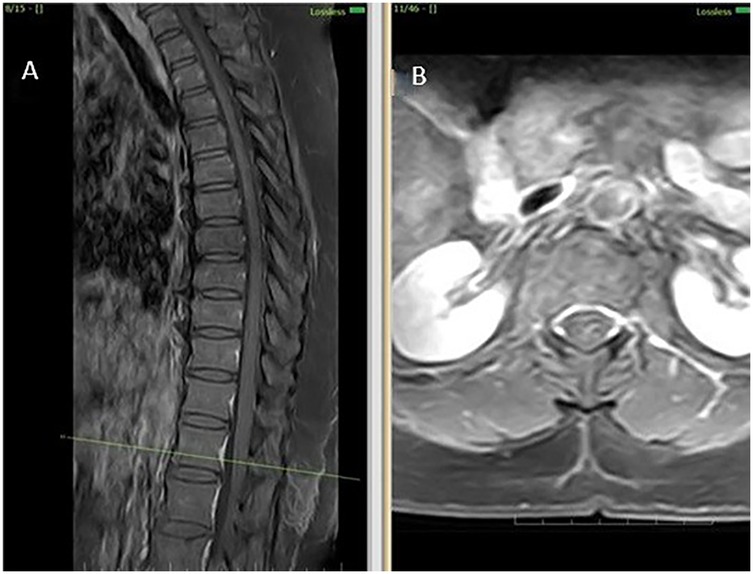

Figure 2

MRI scans showing spine and cross-sectional imagery. Panel A displays a sagittal view of the spine with vertebrae clearly visible. Panel B shows an axial view with surrounding tissues.

Figure 2. MRI thoracolumbar spine findings suggestive of sulcal artery infarction. (A) Sagittal post-contrast T1-weighted image reveals no contrast enhancement at the lesion site, ruling out inflammatory or neoplastic causes. (B) Axial post-contrast T1-weighted MRI confirms absence of mass effect or enhancement, supporting a non-compressive vascular etiology.

Initial investigations (CBC, ESR, CRP, renal and liver function, echocardiography, ECG) were unremarkable. MRI thoracolumbar spine was performed 1 month and 28 days after symptom onset. MRI brain showed no signs of infarction or demyelination. MRI thoracolumbar spine demonstrated T2 and STIR hyperintensity involving the anterior horn and intermediate zone of the left hemicord at D12-L1, without contrast enhancement or mass effect. There was no evidence of cord compression, hematoma, or abscess (Figures 2A–D). MRI of the cervical and lumbar spine showed spondylotic changes with no significant cord involvement (Figures 3A,B). Poor-quality DWI was obtained, limiting diagnostic utility (acknowledged as a limitation). No follow-up MRI was performed.